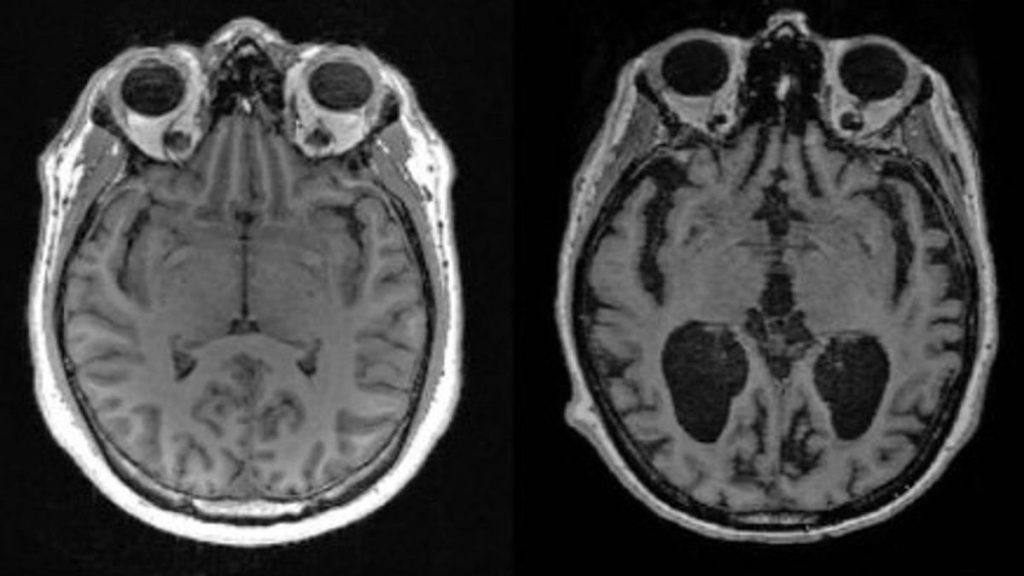

Científicos de la Facultad de Medicina de Harvard descubrieron que la pérdida de litio en el cerebro humano es uno de los primeros cambios que conducen al Alzheimer, mientras que en ratones, una depleción similar de litio aceleraba el deterioro de la memoria.

Décadas de estudios han demostrado que la enfermedad de Alzheimer implica una serie de anomalías cerebrales, entre las que se encuentran los cúmulos de la proteína beta amiloide, los embrollos de la proteína tau y la pérdida de la proteína protectora del cerebro REST.

Sin embargo, estas anomalías nunca han explicado del todo la enfermedad.